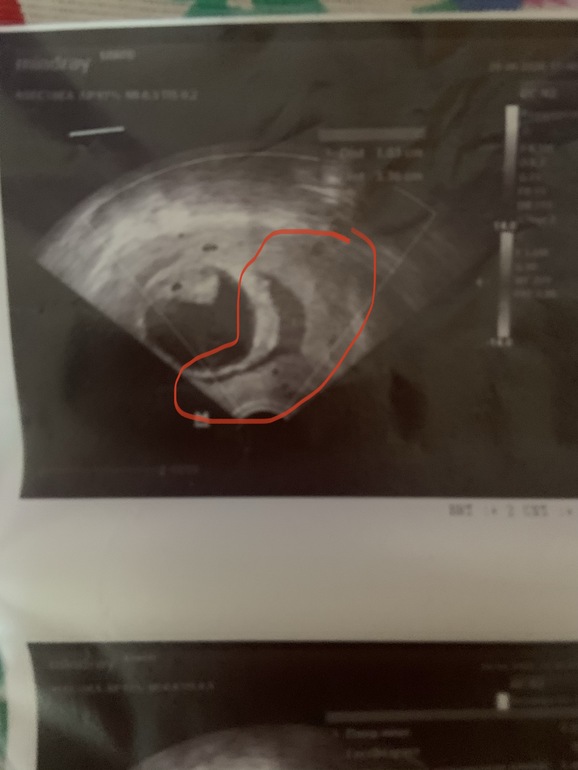

На УЗИ сгустков никаких нет, трансвагинальный датчик тоже чистый, гематома по задней стенке так и остается, зараза 😒 Стала в 2 раза уже, но длинная, как сказала врач, ее прижимает плодный пузырь, как бы сплющивает. Оставляет поддержку утрожестаном 200 утро/вечер и добавить в обед 2таб дюфастона.

Развивается хорошо, на 10+3, СБ 146 ударов 💓